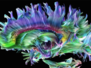

Developing better means of screening for and identifying useful drugs is a key step towards more effective and accessible treatments for patients, especially in poorer parts of the world. Visceral leishmaniasis, caused by infection with Leishmania parasites, is one potentially deadly disease for which more easily distributable treatments are badly needed. Drugs currently available are either very expensive or require a long period of hospitalisation, and can have serious side effects. To identify more suitable medicines, researchers tested the effect of over 170 compounds on macrophages, cells of the immune system, infected with Leishmania parasites (pictured with cell nuclei in red and parasites in green). They monitored the impact of each potential drug on disease progression over several days to measure their speed of action, a key parameter in determining the most effective compounds. Further work on the drugs identified in this assay could yield new treatments in the future.